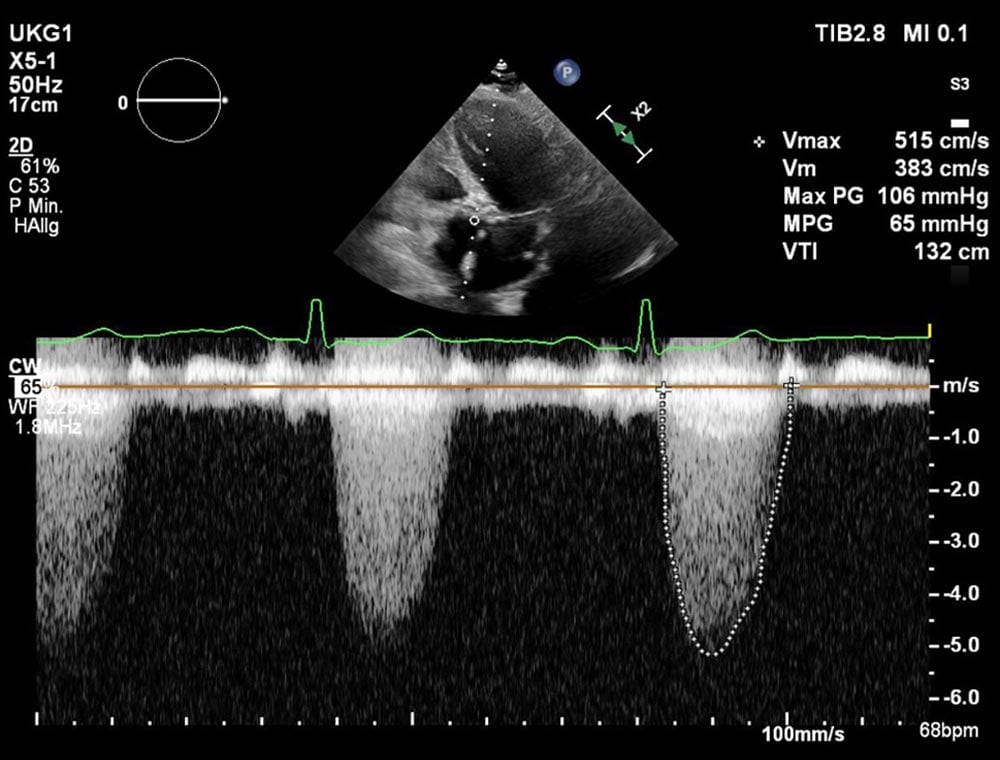

Die postprozedurale transthorakale Echokardiographie zeigte ein gutes Ergebnis mit einem mittleren Aortenklappengradienten von 8 mmHg und einer trivialen bis geringgradigen paravalvulären Aortenklappenregurgitation (Abbildung 10, Video 8). Das EKG zeigte einen neuen Linksschenkelblock ohne weitere Überleitungsstörungen.

Abbildung 10: Postprozedurales TTE